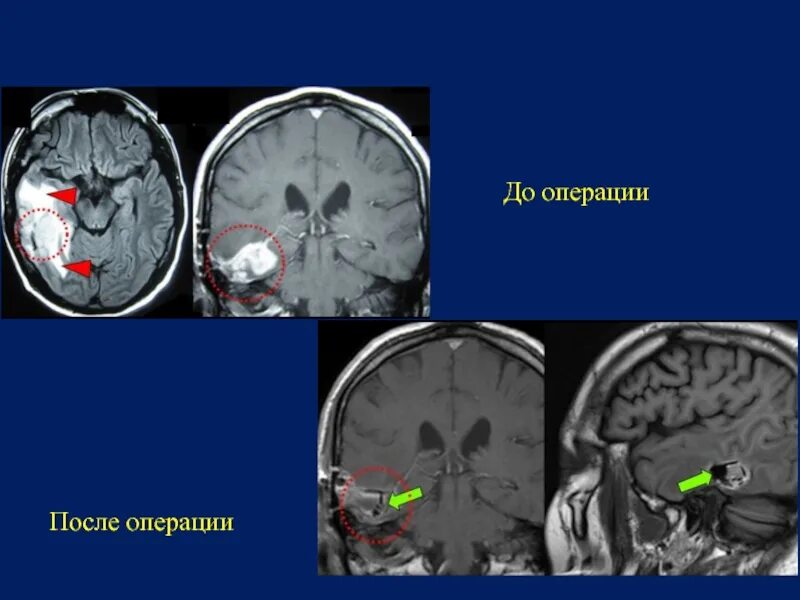

Отек головного мозга операции